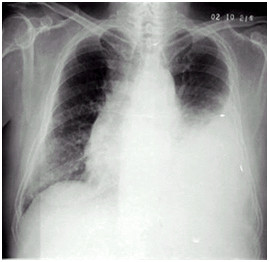

临床助理执业医师实践技能第一站【X线-胸腔积液】知识点模拟题